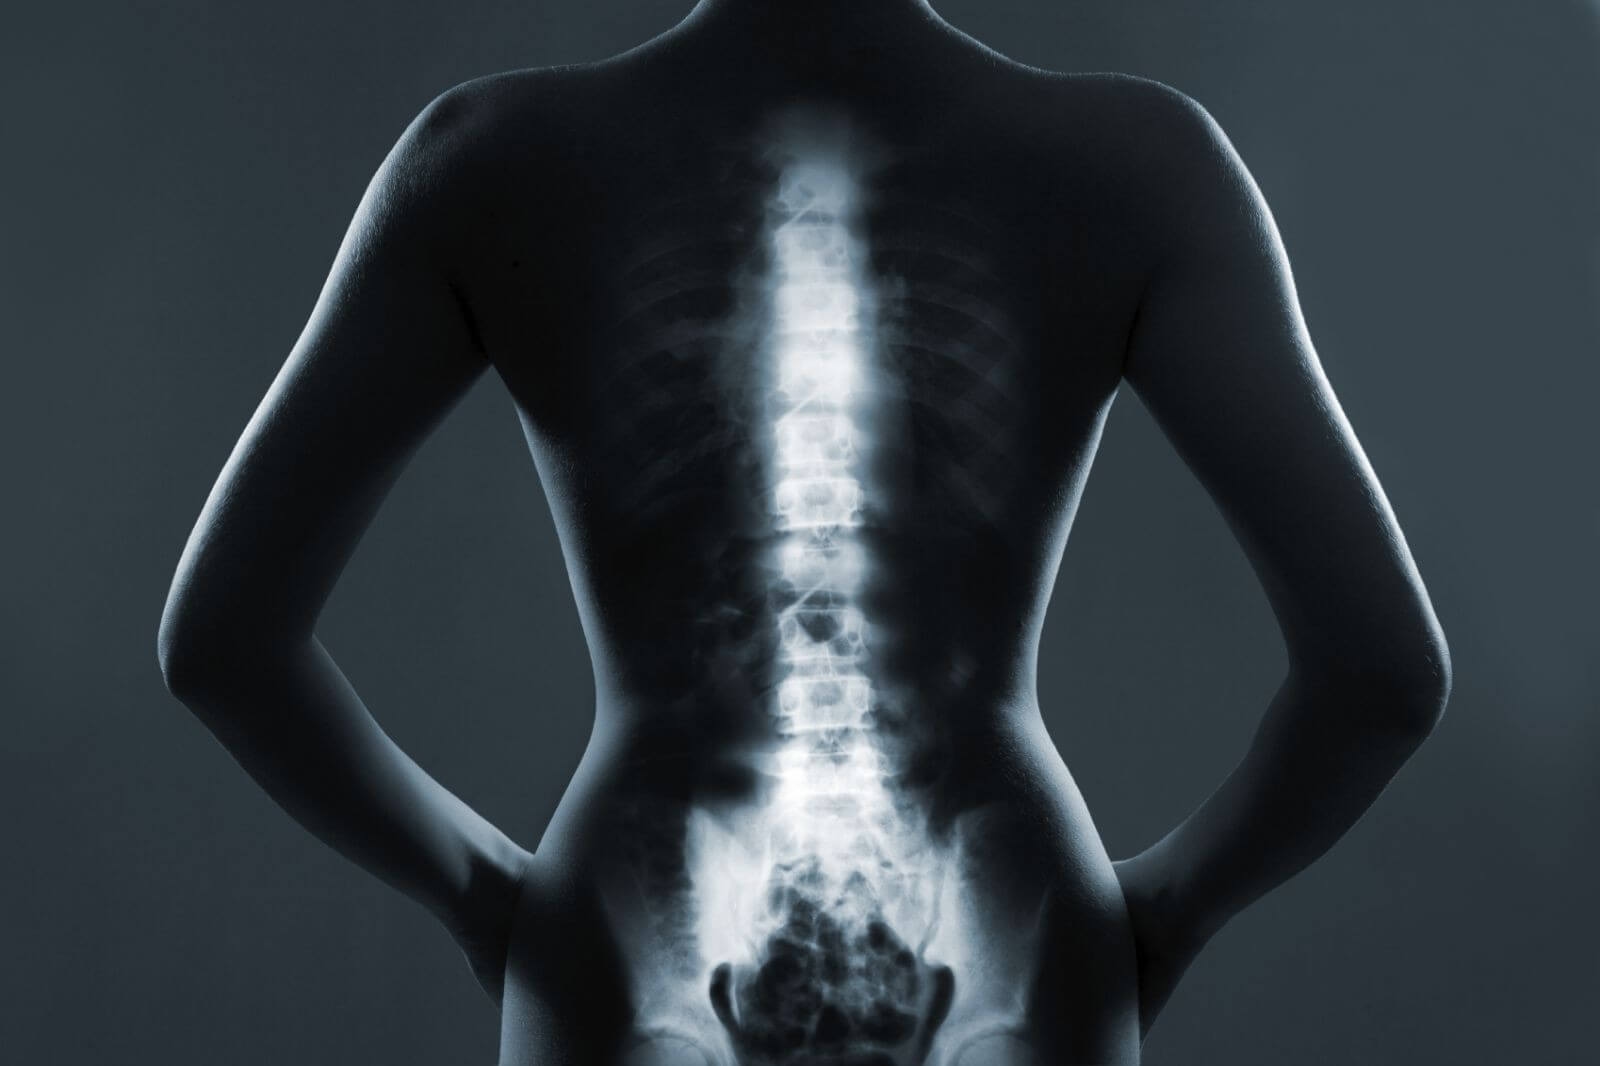

Множинна мієлома – злоякісне ураження кісткового мозку, характерне для осіб після 60–65 років, основні прояви – ниючий біль у спині, ребрах, переломи, анемія, загальна слабкість.

Множинна мієлома часто проявляється у вигляді тривалого болю у спині, хребті, ребрах, з поступовою появою анемії та крихкістю кісток.